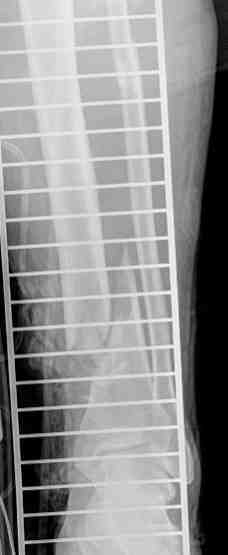

Сегодня попробовали на бедре дистрактор с гексаподно поставленными телескопическими стержнями (см. картинки)-

в общем, даже стандартные детали работают. Хотя шаровые шарниры правильнее будут.